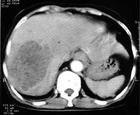

CT檢查

可見單個或多個圓形或卵圓形界限清楚、密度不均的低密區,內可見氣泡。增強掃描膿腔密度無變化,腔壁有密度不